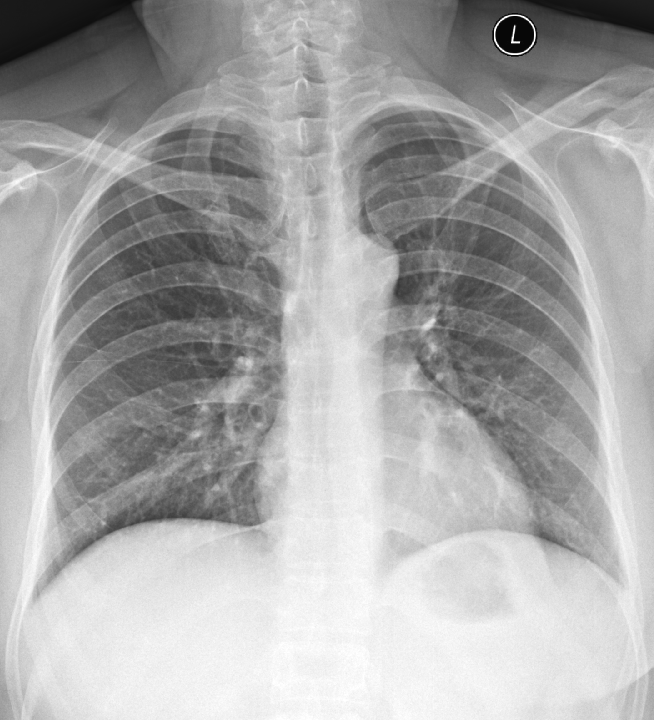

動態(tài)平板DR攝影系統(tǒng)在對胸部的攝影檢查中能夠高清晰度顯示肺組織的結(jié)構,為肺部疾病提供了有價值的科學依據(jù)。

c、胸部

適應癥:氣管支氣管病變;肺部病變(先天性發(fā)育異常、炎癥、結(jié)核、腫瘤、寄生蟲病變等);心臟病變(心包積液、心包炎、先天及后天性心血管病等);胸膜病變(胸膜炎、胸膜腫瘤等);縱膈病變(氣腫、腫瘤等)。